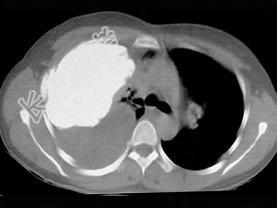

- 单项选择题男,66岁, 剧烈胸痛,请结合CT图像, 选择最可能的诊断 ( )

A、右侧胸腔积液胸膜钙化

B、右肺癌侵犯胸膜

C、右侧胸膜间皮瘤

D、右侧肺不张

E、右侧肺肺癌